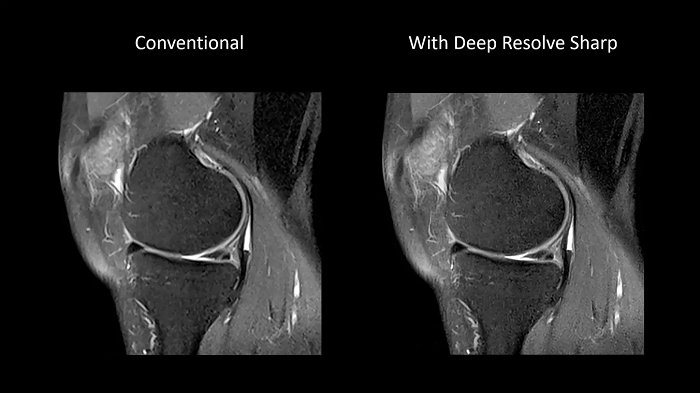

Deep Resolve Sharp

Using a convolutional neural network of TSE sequences, Deep Resolve Sharp produces high-resolution images from low-resolution input. Sharper and crisper images can be achieved without compromising on data acquisition time.

Image Courtesy: University Hospital Erlangen, Germany | Image-ID: 4aaaa0459